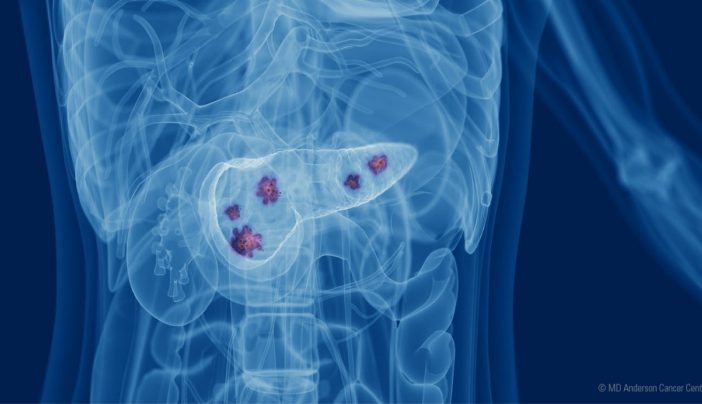

Pancreatic Cancer After Whipple Surgery

Pancreatic Cancer After Whipple Surgery

Pancreatic Cancer Treatment 2024 Kimmi Charmine

Pancreatic Cancer After Whipple Surgery - [desc-14]